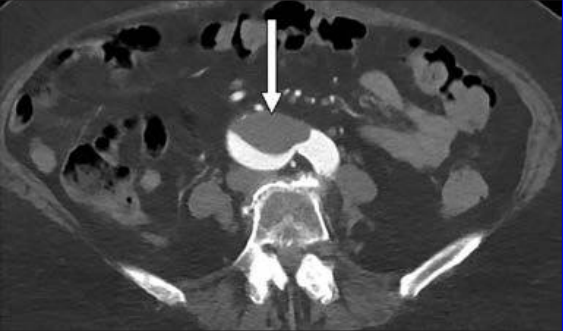

This photo gallery shows the variety of radiological presentations of COVID-19 (SARS-CoV-2) in medical imaging, including computed tomography (CT), radiograph X-rays, ultrasound, echocardiograms and magnetic resonance imaging (MRI). The radiology images show examples of typical COVID pneumonia in the lungs and the numerous complications the virus causes in the body in multiple organs, including the brain, kidneys, heart, abdomen and vascular system.